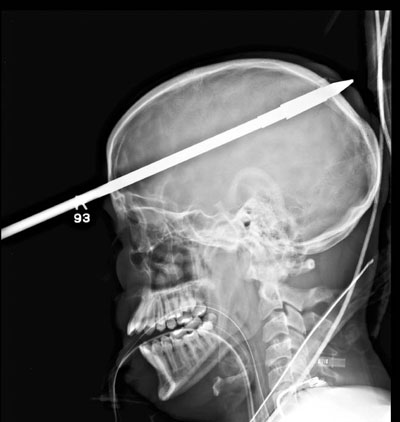

3呎魚叉穿腦奇蹟不死

美國佛羅里達州16歲少年洛佩斯早前偕朋友到湖邊暢泳捕魚,其間朋友不小心發射魚槍,魚叉從洛佩斯的右眼對上一吋直插右腦(見圖),他竟然奇蹟不死,簡直是奇蹟!

醫生形容這是不尋常案例︰傷者頭部插著3呎長魚叉,但神志清醒;醫院直升機到達時,傷者揮動雙手,口中則說著西班牙文。

醫生先為洛佩斯麻醉,而腦神經外科醫生說,當時最緊要是抗拒將魚叉直拔出來的衝動,院方於是向消防局借來鋼筋切割器和老虎鉗,先切掉魚叉的18吋外露部分,再開刀3小時拿出頭顱內的部分,幸好沒破壞主要血管。洛佩斯情況一度嚴重,且有輕微失憶,但康復進度驚人,已能簡單說話,預料留院2至3個月便可完全康復。  ■《每日郵報》